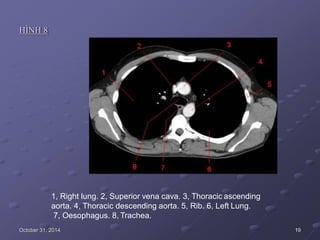

HÌNH 8

1, Right lung. 2, Superior vena cava. 3, Thoracic ascending

aorta. 4, Thoracic descending aorta. 5, Rib. 6, Left Lung.

7, Oesophagus. 8, Trachea.

October 31, 2014 19